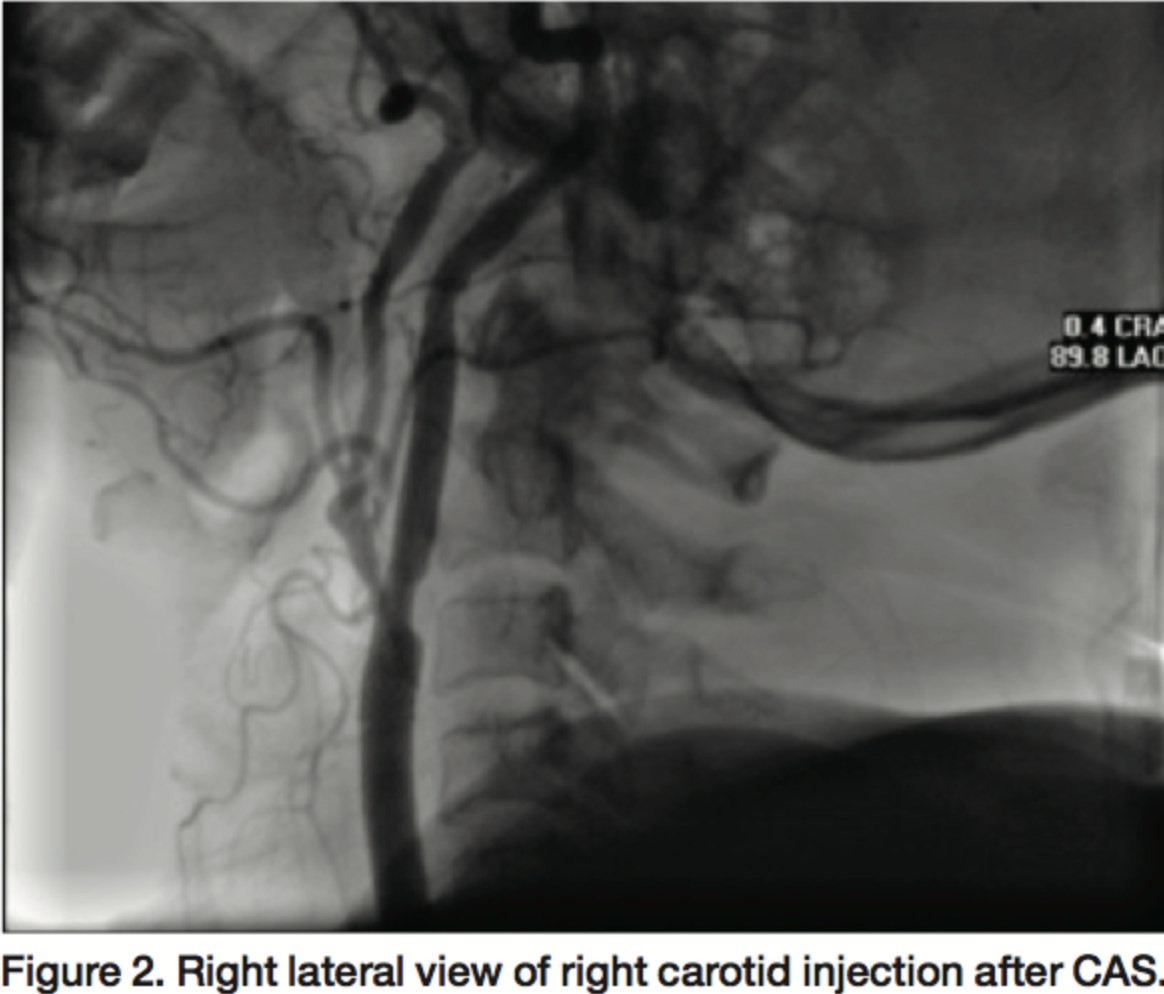

A 51-year-old female patient with history of diabetes mellitus, hypertension, hyperlipidemia and 3-vessel disease with left ventricular ejection fraction (LVEF) of 55% was a good candidate for coronary artery bypass graft (CABG) due to refractory chest pain. We proceeded with stenting of the right internal carotid because of a calcified plaque with 90% stenosis proximal to the right internal carotid without bulb involvement (Figures 1 and 2). The left internal carotid had a plaque with <50% stenosis. Her blood pressure was 120/80 before the procedure but she had severe prolonged hypotension (70 mmHg/p) after the procedure. By treatment with saline and dopamine, her blood pressure preserved about 120 to 130 mmHg but with a modest decrease in dose of dopamine (decreasing from 15 µg/kg/min to 12 µg/kg/min over 5 days); systolic blood pressure (SBP) dropped to 80 mmHg. This situation took 7 days and improved only after tight control of her blood sugar. Fasting blood sugar (FBS) was 96 mg/dL before and remained high despite divided doses of regular insulin (Table 1).